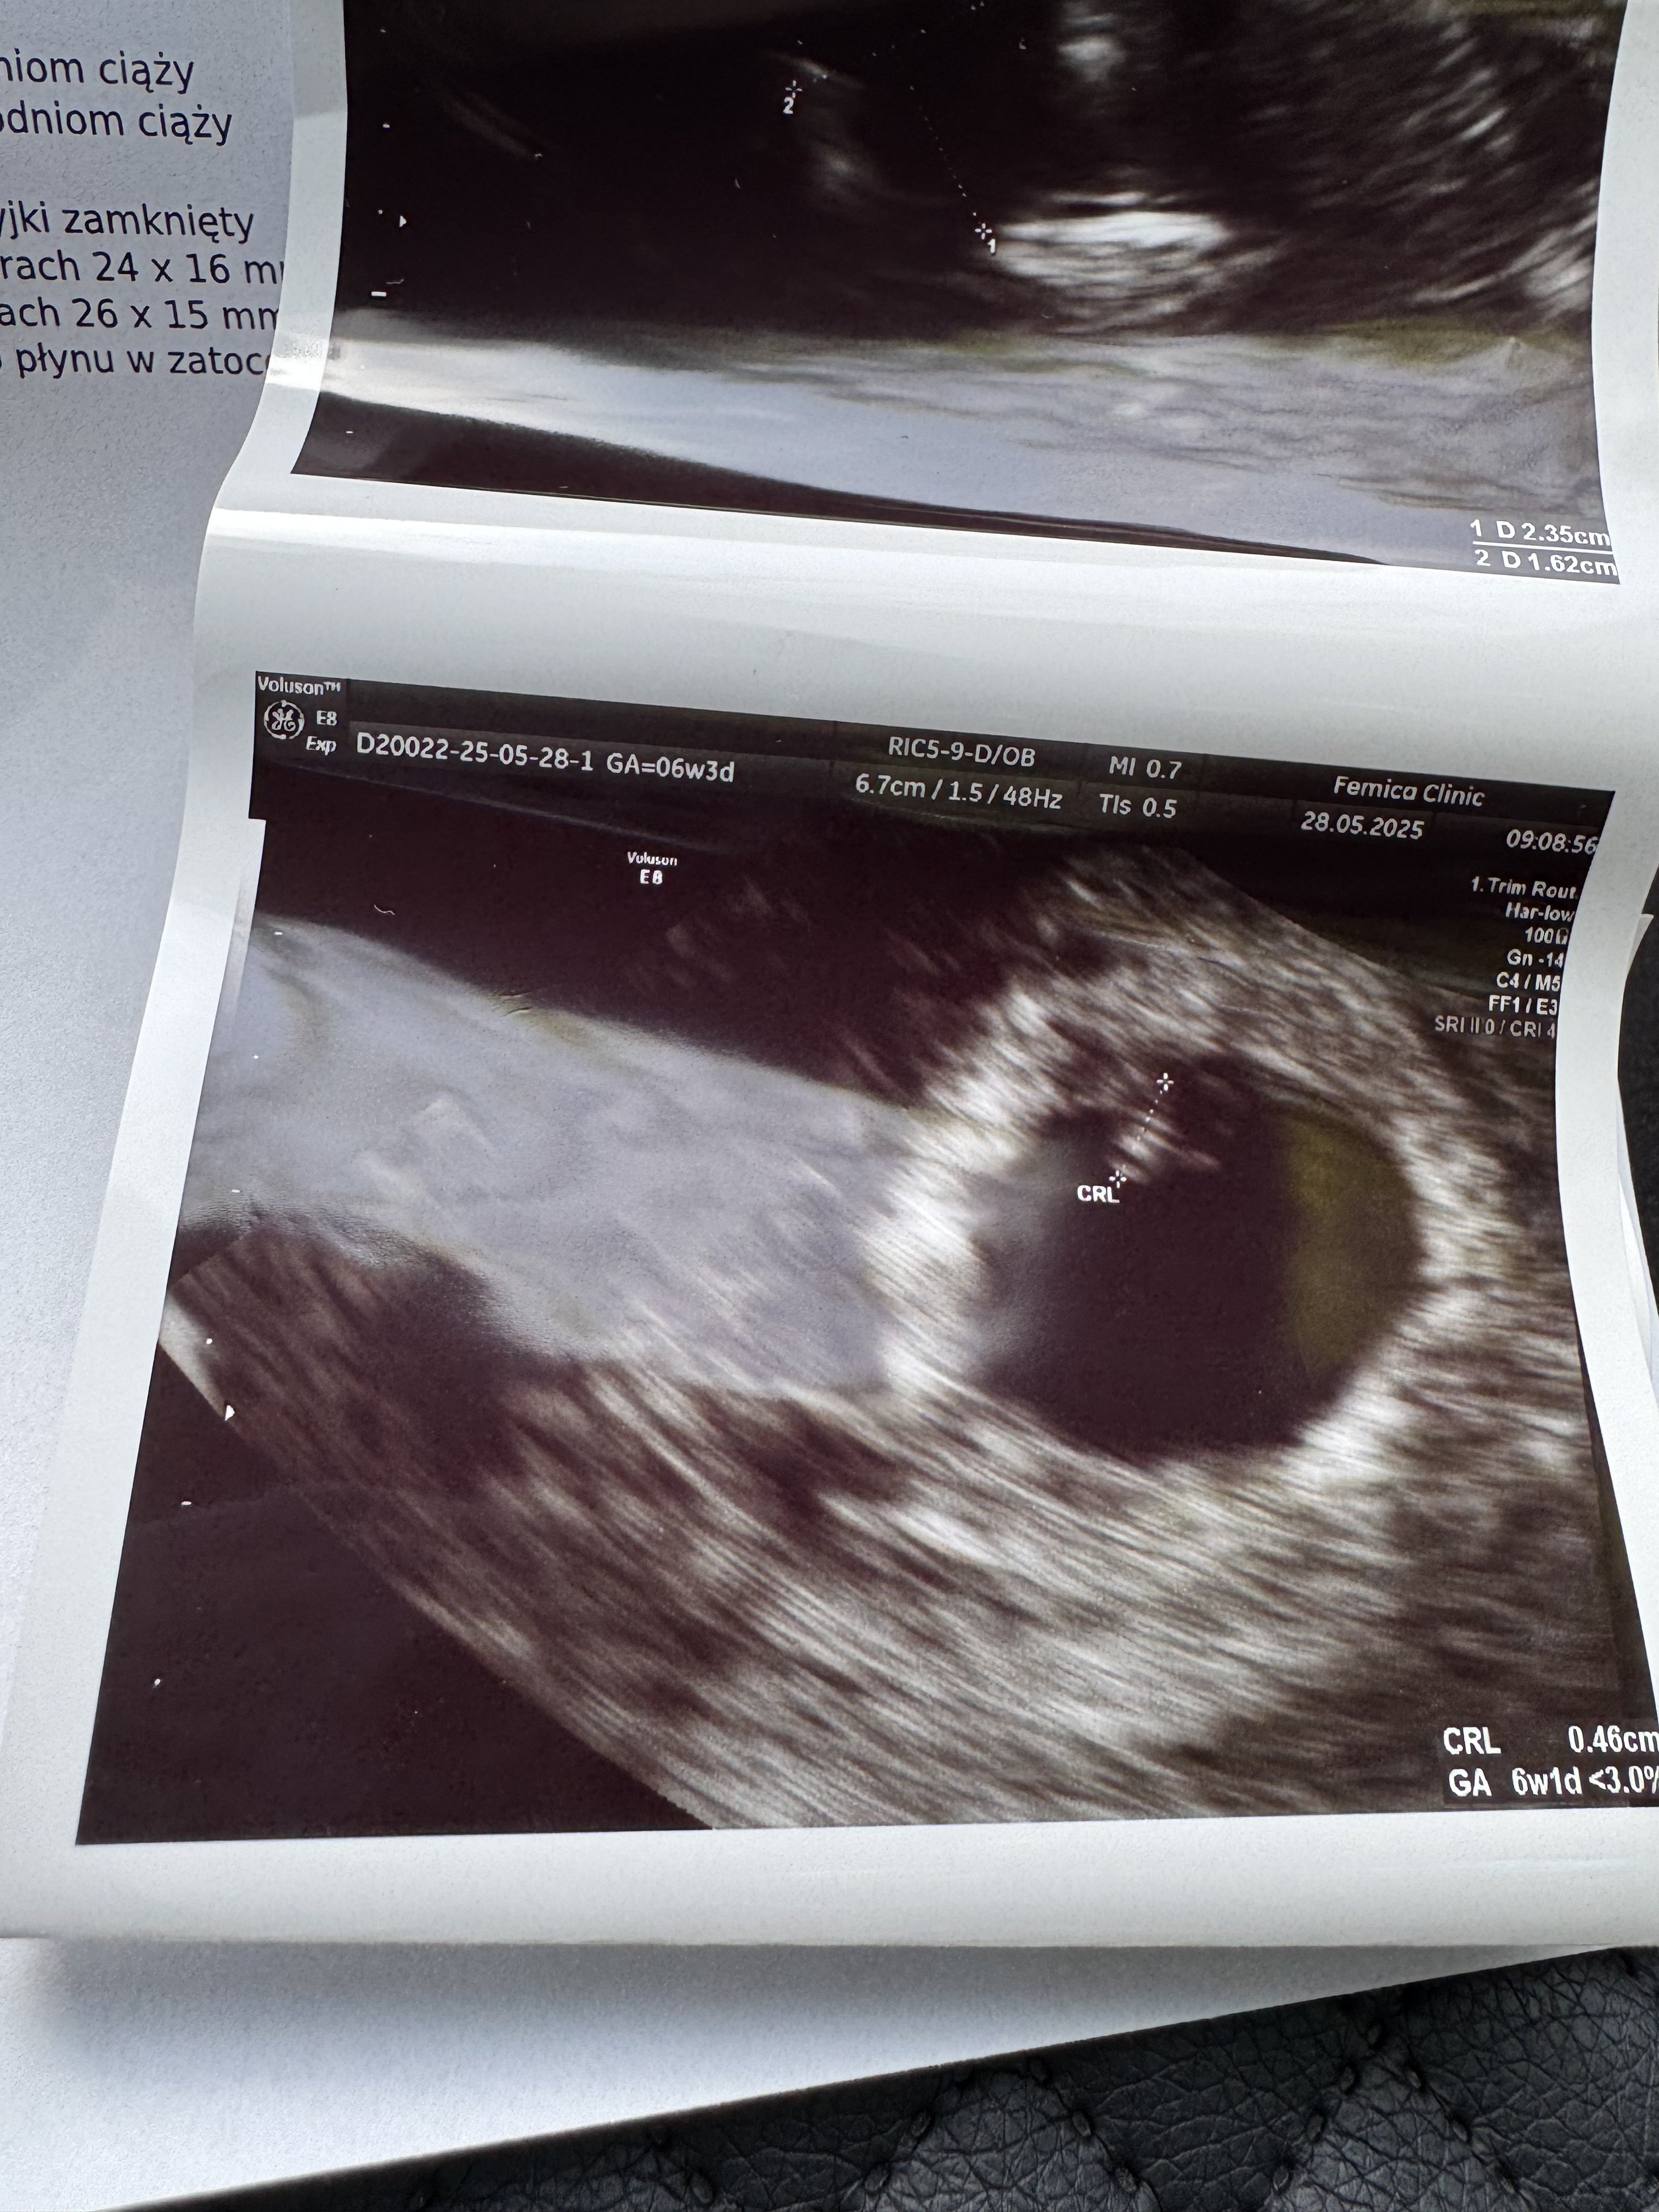

Mamy małego dzidziusia z bijącym serduszkiem . Wszystko jest w porządku. Serduszko bije poprawnie. Przed 10tyg powiedziała doktor że nie słucha się bicia serduszka. Termin porodu na 18 stycznia

Załączniki

• IMG_1754.jpeg

IMG_1754.jpeg

1,4 MB · Wyświetleń: 77